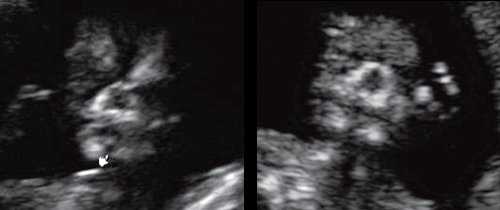

При эхографии в срок 13 недель 3 дня фетометрические параметры плода соответствовали гестационной норме, толщина воротникового пространства составила 1,5 мм; длина костей носа - по 2,5 мм. При трансвагинальном сканировании были обнаружены: затылочное энцефалоцеле размерами 7,4х3,5х3,7 мм (рис. 1), полидактилия кистей (рис. 2), увеличенные кистозно-измененные почки: правая - 28,5х21,3 мм; левая - 26,4х18,7 мм (рис. 3). Объем амниотической полости был нормальным для данного срока.

(Слева) Тот же плод. УЗИ брюшной полости, фронтальная плоскость. С обеих сторон определяются увеличенные кистозно-измененные почки. Необходимо помнить, что объем амниотической жидкости в I триместре может быть в норме, даже несмотря на тяжелое двустороннее поражение почек.

(Справа) Во время скринингового УЗИ плода в I триместре, выполненного во время последующей беременности у той же женщины, обнаружено энцефалоцеле. Синдром Меккеля-Грубера имеет аутосомно-рецессивный тип наследования, риск повторного возникновения составляет 25%.